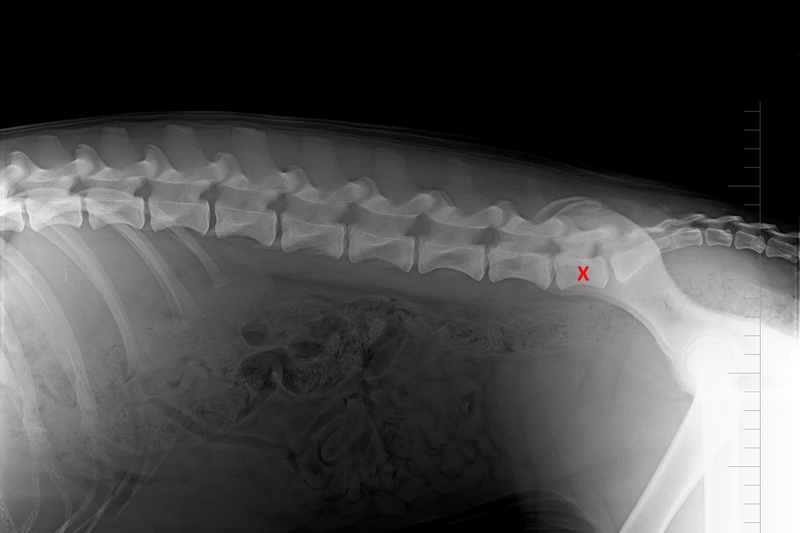

Ke zjištění počtu bederních obratlů bývá jako upřesňující využívána laterolaterální projekce, kdy pes leží na boku. Na naší klinice k upřesnění diagnózy dále provádíme RTG vyšetření bederní páteře a kosti křížové ve ventrodorsální projekci, jež nám umožnilo v několika případech diagnostikovat i thorakolumbální přechodový obratel (lokalizovaný na přechodu hrudní a bederní páteře) a také tzv. laterální spondylózu.

Rentgenovým vyšetřením lze snadno odhalit přechodový obratel již ve štěněčím věku, ideálně v kombinaci poloh „na boku“ a „na zádech“.

(1)+(2): Raná diagnostika je možná a snadno proveditelná již v 7 týdnech stáří štěňat

(3) –(5): Potvrzení diagnózy u stejné feny ve stáří 7 měsíců